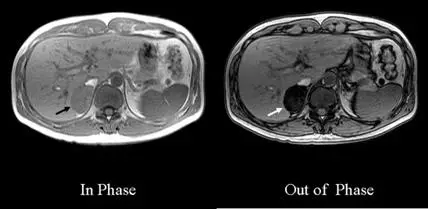

下圖為磁振影像,箭號所指之腎上腺腫瘤在梯度回音技術( gradient-echo techniques )之聚相( In Phase )及失相( Out of Phase )影像中的變化,顯示此腫瘤含有何種成分? 圖片

影像呈現兩張軸切面梯度回音 T1 加權影像,左側標示「In Phase」(聚相),右側標示「Out of Phase」(失相)。

• 聚相影像(In Phase):腎上腺區域可見一腫瘤(箭號所指),其訊號強度與周圍軟組織相近,顯示為中等灰階亮度的圓形腫塊。

• 失相影像(Out of Phase):同一腎上腺腫瘤出現明顯訊號下降(signal dropout),病灶在失相影像中顯著變暗,與聚相影像形成強烈對比。

此種「失相影像訊號明顯低於聚相影像」的現象,是細胞內微小脂肪(intracytoplasmic/microscopic fat)的典型表現,即脂肪豐富型腎上腺腺瘤(lipid-rich adrenal adenoma)的診斷特徵。